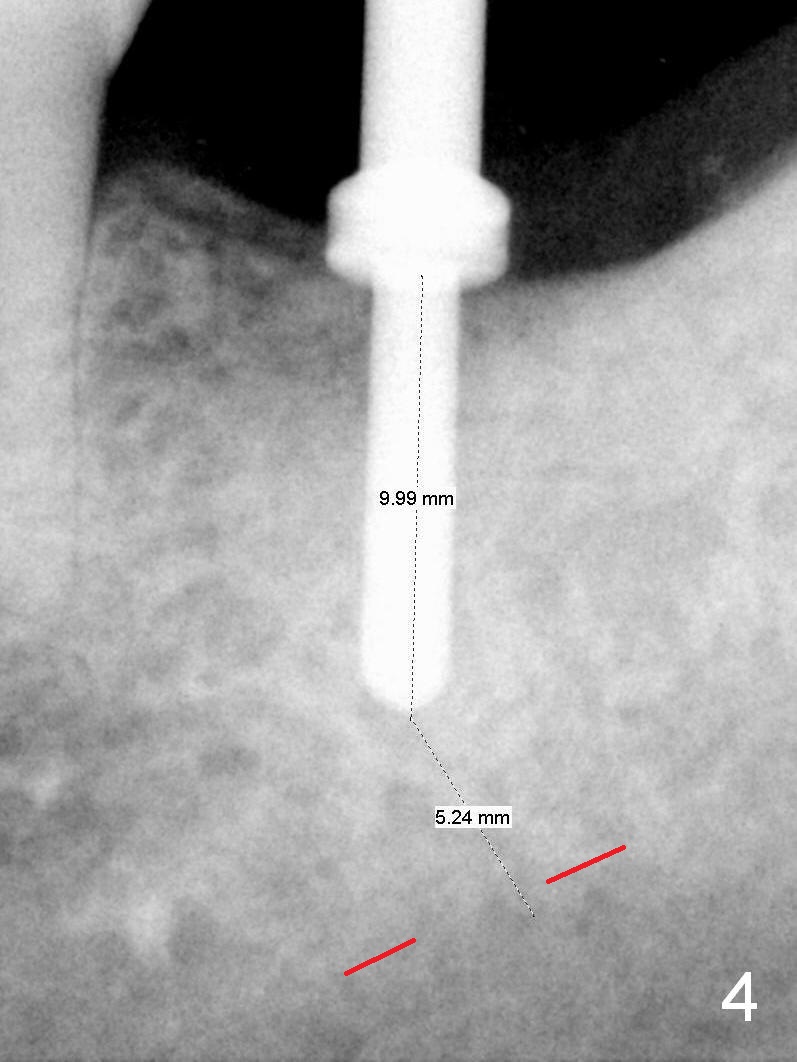

A 48-year-old lady is a dental phobic, requesting extraction of the lower left 2nd molar (Fig.1).   She returns for implant placement 9 months post extraction (Fig.2).  The ridge is mildly to moderately atrophic.  It appears that a 5x12 mm implant is appropriate for the site (Fig.3).  For safety, osteotomy is initiated at the depth of 10 mm; it appears that there is enough height for a 12 mm implant (Fig.4).  The depth is controlled by drill stopper (Fig.5 S).  Finally a 5x12 mm implant is apparently safely placed (Fig.6).  A healing abutment is placed and the incision is sutured with 4-0 Chromic gut (Fig.7).  Perio dressing is applied around the healing abutment for wound protection (Fig.8).  It appears that the healing abutment (Fig.8': *) helps stabilize the perio dressing, which remains in place 1 week postop.  When the perio dressing is removed, the wound around the healing abutment is healing (Fig.9).  There is no bone loss around the implant 3 months postop (Fig.10 (H: healing abutment), or 16 months postop (i.e., 9 months post cementation, Fig.11,12).  The patient complains of pain when she chews with the implant crown, but pain stops whenever she does not bite.  Percussion does not elicit any discomfort.  The gingiva is healthy.  There is possibility of the buccal plate being thin or the lingual plate being perforated in the submandibular fossa.  If the discomfort remains the same next 6 months, CBCT will be prescribed.